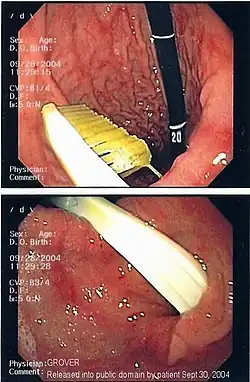

Commonly swallowed objects include coins, buttons, batteries, and small bones (such as fish bones),[1] but can include more complex objects, such as eyeglasses,[5] spoons,[6] and toothbrushes[5] (see image).

Once the foreign body has been identified with the gastroscope, various devices can be passed through the gastroscope to grasp or manipulate the foreign body. Devices used include forceps, which come in varying shapes, sizes and grips,[12] snares, and oval loops that can be retracted from outside the gastroscope to lasso objects,[13] as well as Roth baskets (mesh nets that can be closed to trap small objects),[14] and magnets placed at the end of the scope or at the end of orogastric tubes.[12][15] Some techniques have been described that use foley catheters to trap objects, or use two snares to orient foreign bodies.[6]